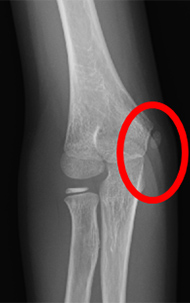

内側型野球肘の画像

肘の内側

正常

(レントゲン)

内側上顆裂離骨折